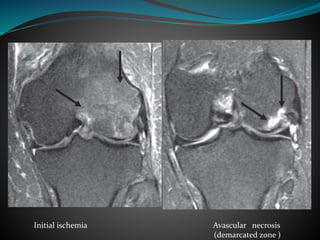

 Initial ischemia- Large area of ill defined marrow

edema

 If ischemia persists- avascular necrosis of bone occur

in subchondral portion manifested as single or double

rim of demarcation and may have appearance of fat,

edema,blood or sclerosis

Initial ischemia Avascular necrosis

(demarcated zone )